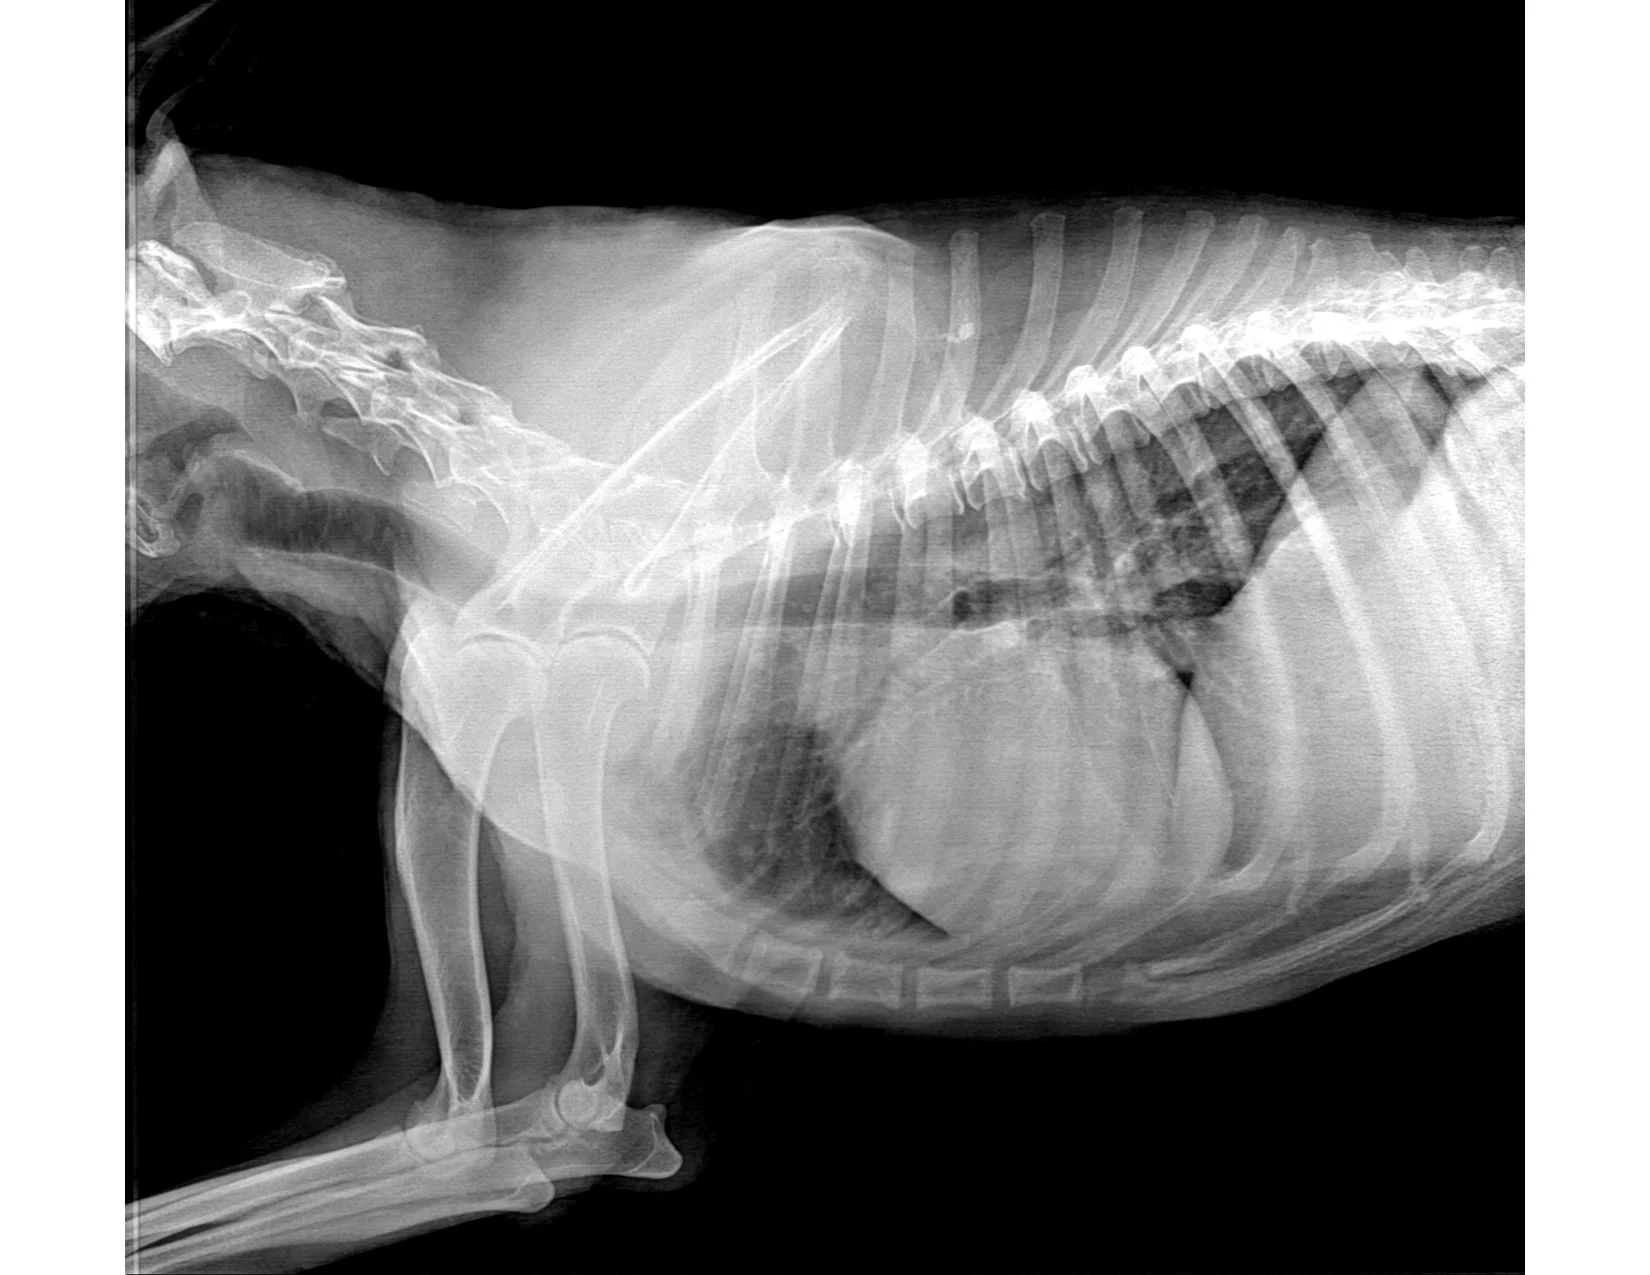

This is the x-ray the vet showed me to illustrate that my dog was dying of bone cancer. It confirmed her diagnosis.

She said, “It’s there, see?” pointing a wooden stick along his spine and forearm.

I keep looking at the x-ray for cancer. I still don’t see it.